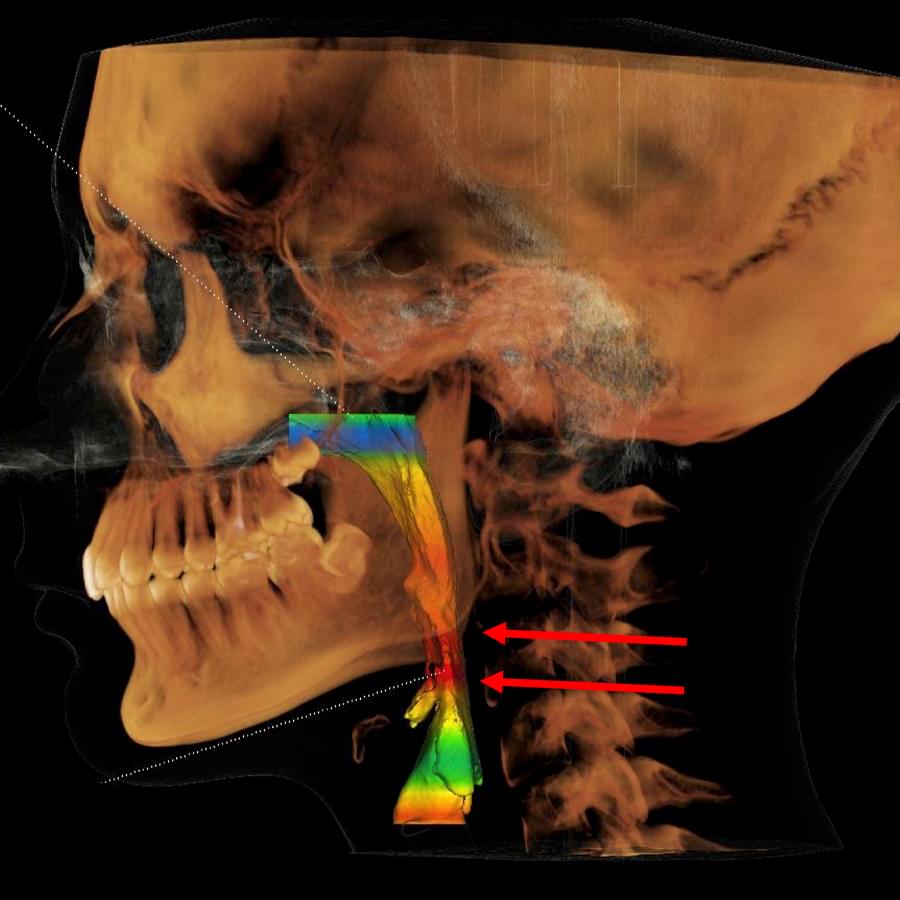

3D цефалометричний аналіз є сучасною технологією, яка дозволяє отримувати точніші,

комплексніші та надійніші дані про зубну та скелетну структуру. Ця технологія може стати

великим кроком в перед для ортодонтів, які хочуть забезпечити найкраще можливе лікування

своїх пацієнтів.

Основні переваги 3D цефалометричного аналізу:

Точність: 3D цефалометричний аналіз забезпечує точніше визначення розмірів та відстаней між

зубами та кістковими структурами.

Комплексність: ця технологія дозволяє отримувати детальні дані про різні структури, такі як

кістка та м'язи, що дозволяє ортодонтам докладніше досліджувати деякі патології та планувати

лікування.

Надійність: 3D цефалометричний аналіз дозволяє отримувати надійніші результати, оскільки

виключає можливість помилок, пов'язаних зі спотворенням або перекриттям зображень.